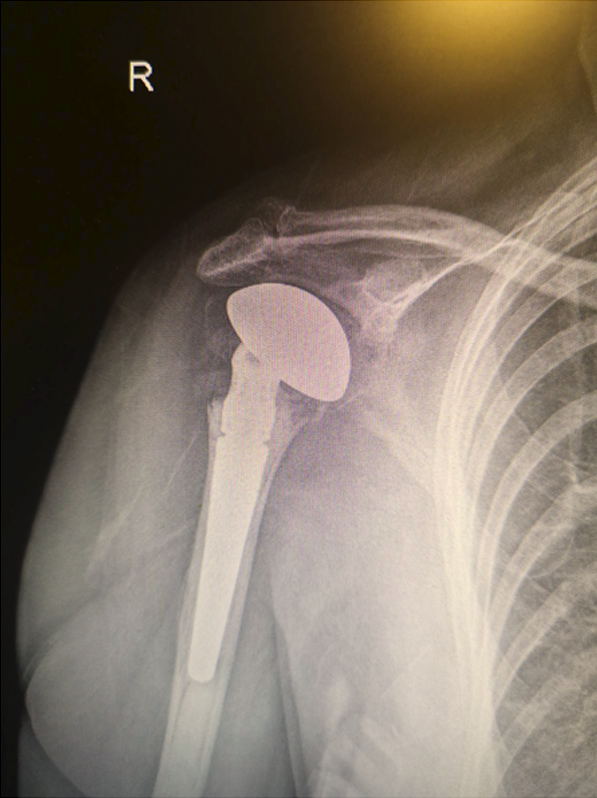

Veštačko rame

U određenim indikacijama, u kojima ne može da pomogne ni artroskopsko lečenje ramena, potrebna je ugradnja veštačkog ramena (proteze), koja se izvodi isključivo standardnom otvorenom operacijom.Veštačko rame je terapija izbora ne samo kod preloma ramena već i kod oštećenje zgloba ramena usled degenerativnih promena, upalnih procesa, ili drugih povreda.

Kao i veštački kuk ili koleno, i proteze za rame su, prema rečima dr Medenice, na vrlo visokom tehnološkom nivou. Dva su osnovna tipa proteza za rame: anatomske i reverzne. Anatomske, ili fracture tipe proteze, koriste se kod preloma zgloba ramena i drugih zglobnih oštećenja, pod uslovom da su kod pacijenta potpuno očuvani mišići rotatorne manžetne - oni stabilizuju rameni zglob, pa tako i samu protezu. Reverzna proteza ramena je, pak, specijalno veštačko rame razvijeno s ciljem da se pomogne i osobama sa pokidanim tetivama rotatorne manžetne i nefunkcionalnim rotatornim mišićima; reverzna proteza je dizajnirana tako da je za podizanje ruke dovoljan samo rad deltoidnog mišića.

Proteze za rame mogu da budu totalne i parcijalne. U novije vreme su u primeni i proteze namenjene isključivo zameni oštećene hrskavice, na primer. |

Iz foto dokumentacije dr Medenice: Proteza ramena |